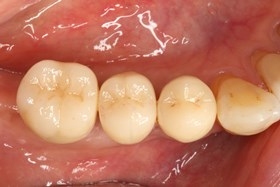

![銀髮族植牙 銀髮族植牙]()

植牙後癒合狀況良好